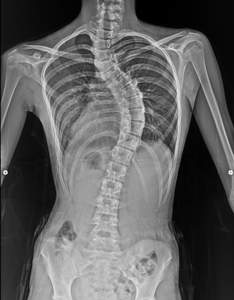

手術前のレントゲン画像